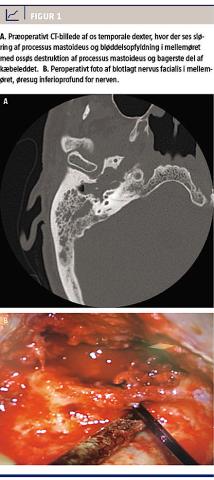

En 72-årig mand, der ikke havde forudgående øreproblematik, blev henvist til et lokalsygehus på grund af højresidig otalgi, øreflåd, intermitterende højresidig perifer facialisparese og reduceret hørelse. Der var ingen svimmelhed eller tinnitus. En initial objektiv undersøgelse viste en polypøs tumor i øregangen ved trommehinden, ingen facialisparese, og en audiometri viste presbyacusis bilateralt samt konduktivt høretab på højre side. En supplerende MR-skanning viste sløring af processus mastoideus og mellemøret på højre side. Initial histologisk undersøgelse af tumoren viste akut og kronisk inflammation samt reaktiv hyperplasi. Videre udredning med CT viste en stor bløddelsopfyldning med knogledestruktion i mellemøret, processus mastoideus, bagerste del af kæbeleddet og basis cranii med blotlæggelse af carotiskanalen (Figur 1A). På mistanke om kolesteatom eller adeno-

matøs tumor blev der udført eksplorativ tympanotomi og mastoidektomi. Der blev her fundet en polyp, der udfyldte hele øregangen, polypøst omdannet trommehinde og i mellemøret store mængder granulationsvæv, knogledestruktion og en særdeles letblødende polypøs tumor. Pga. profus blødning lykkedes det ikke at fjerne alt tumorvæv. Efterfølgende histologisk undersøgelse viste overraskende IP.

Patienten blev derefter henvist til yderligere kirurgisk behandling på Øre-, næse-, halsafdelingen på Rigshospitalet. En præoperativ undersøgelse viste højresidig perifer facialisparese, House-Brackmann grad 3, og en CT viste tumorprogression. Undersø-

Patienten blev senere opereret med højresidig subtotal petrosektomi og blindlukning af øregangen. Peroperativt fandt man tumorvæv i hele mellemøret, processus mastoideus og frem i tubaostiet samt blotlagt dura, arteria carotis interna, vena jugularis interna og nervus facialis, som fremstod ødematøs og misfarvet (Figur 1B). Alt tumorvæv blev fjernet, dog uden garanti for radikalitet mod dura og karskeden. Den endelige histologi viste IP med malign transformation til ikkekeratiniserende planocellulært karcinom. Immunhistokemisk farvning viste P16-over-

ekspression.